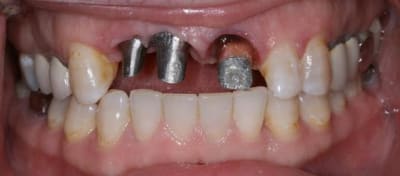

Bon ben j'ai implanté avant d'avoir refait la 21. Du coup j'ai mésialé la pose de 11 pour compenser la distalisation de 21.

Au final je n'ai pas fait de greffe osseuse... et j'ai réalisé une technique de rouleau sur 11-12 mais je reste un peu court à mon goût.

J'ai mis en place des transitoires sur 11-12-21 pour temporiser 3 mois pour voir la maturation des tissus mous.

Je réaliserai dans un second temps des piliers procera.

Je mets quelques photos de la patiente au cab et du prothèsiste d'Epinal.

La vraie difficulté a été de retrouver le milieu incisif pour déterminer la position des implants.

Les provisoires sont solidaires ? ( bravo pour le parallélisme)

Le zénith de la 21 doit être un peu plus distal pour que le résultat soit plus sympa